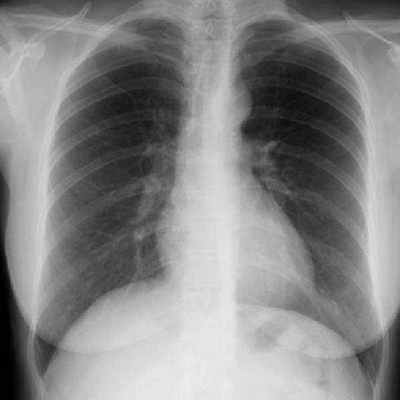

б) Рентгенография затемнения по типу матового стекла:

- Облаковидное затемнение, на фоне которого видны структуры легкого

При пневмониях используются следующие методы лучевой диагностики. Безусловно, все начинается с обзорной рентгенографии органов грудной полости, обязательно проведенной в двух проекциях – в прямой и в боковой проекции. Это исследование используется при начале заболевания и в среднем через 7-10 дней.

Рентгенологические признаки альвеолярной инфильтрации имеют вид участков инфильтрации, как правило, однородной структуры, средней интенсивности. В зоне инфильтрации отчетливо видны воздушные просветы бронхов (так называемый симптом «воздушной бронхографии»).

Инфильтрат широким основанием прилежит к костальной плевре. Интенсивность его уменьшается по направлению к корню легкого. Патологически инфильтрат чаще локализуется в задненижних отделах легких (в пределах 1-2 сегментов, реже в пределах целой доли).

Наиболее типичными рентгенологическими признаками является локальный участок инфильтрации легочной ткани (обычно альвеолярного типа), объем поражения. В настоящее время уже редко встречаются долевые инфильтрации. Обычно это 1-2 сегмента. Изменение обычно носит односторонний характер.

В целом, плевропневмония хорошо выявляется при обычном рентгенологическом исследовании.